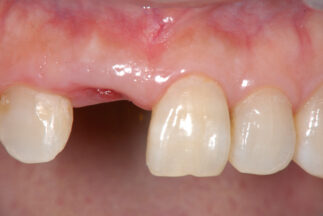

- After